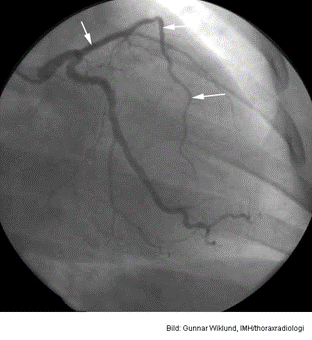

Vad vill vi förmedla med denna bild?

En ST-höjning som har gått i regress